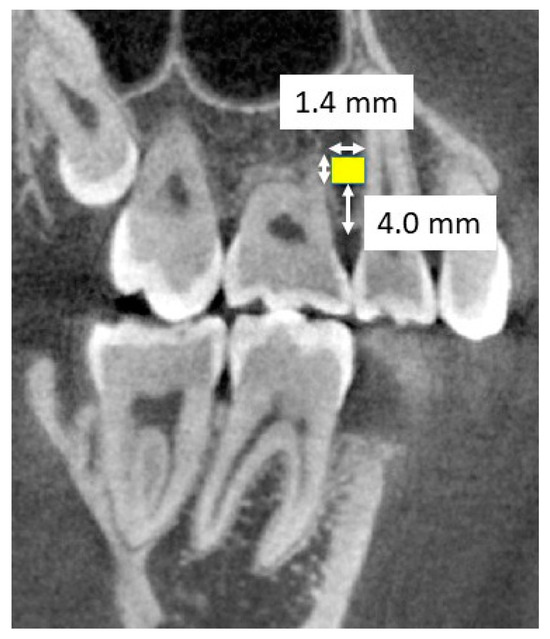

2.2. CBCT Imaging and Image Processing

2.3. Measurements